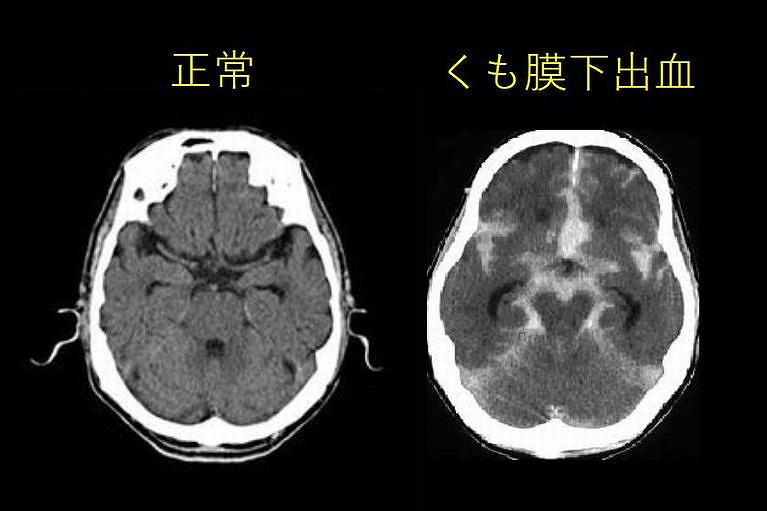

くも膜下出血

• 今までに「経験したことのない」激しい頭痛くも膜下出血

• 今までで「最悪」の頭痛

• いつもの頭痛と明らかに違う